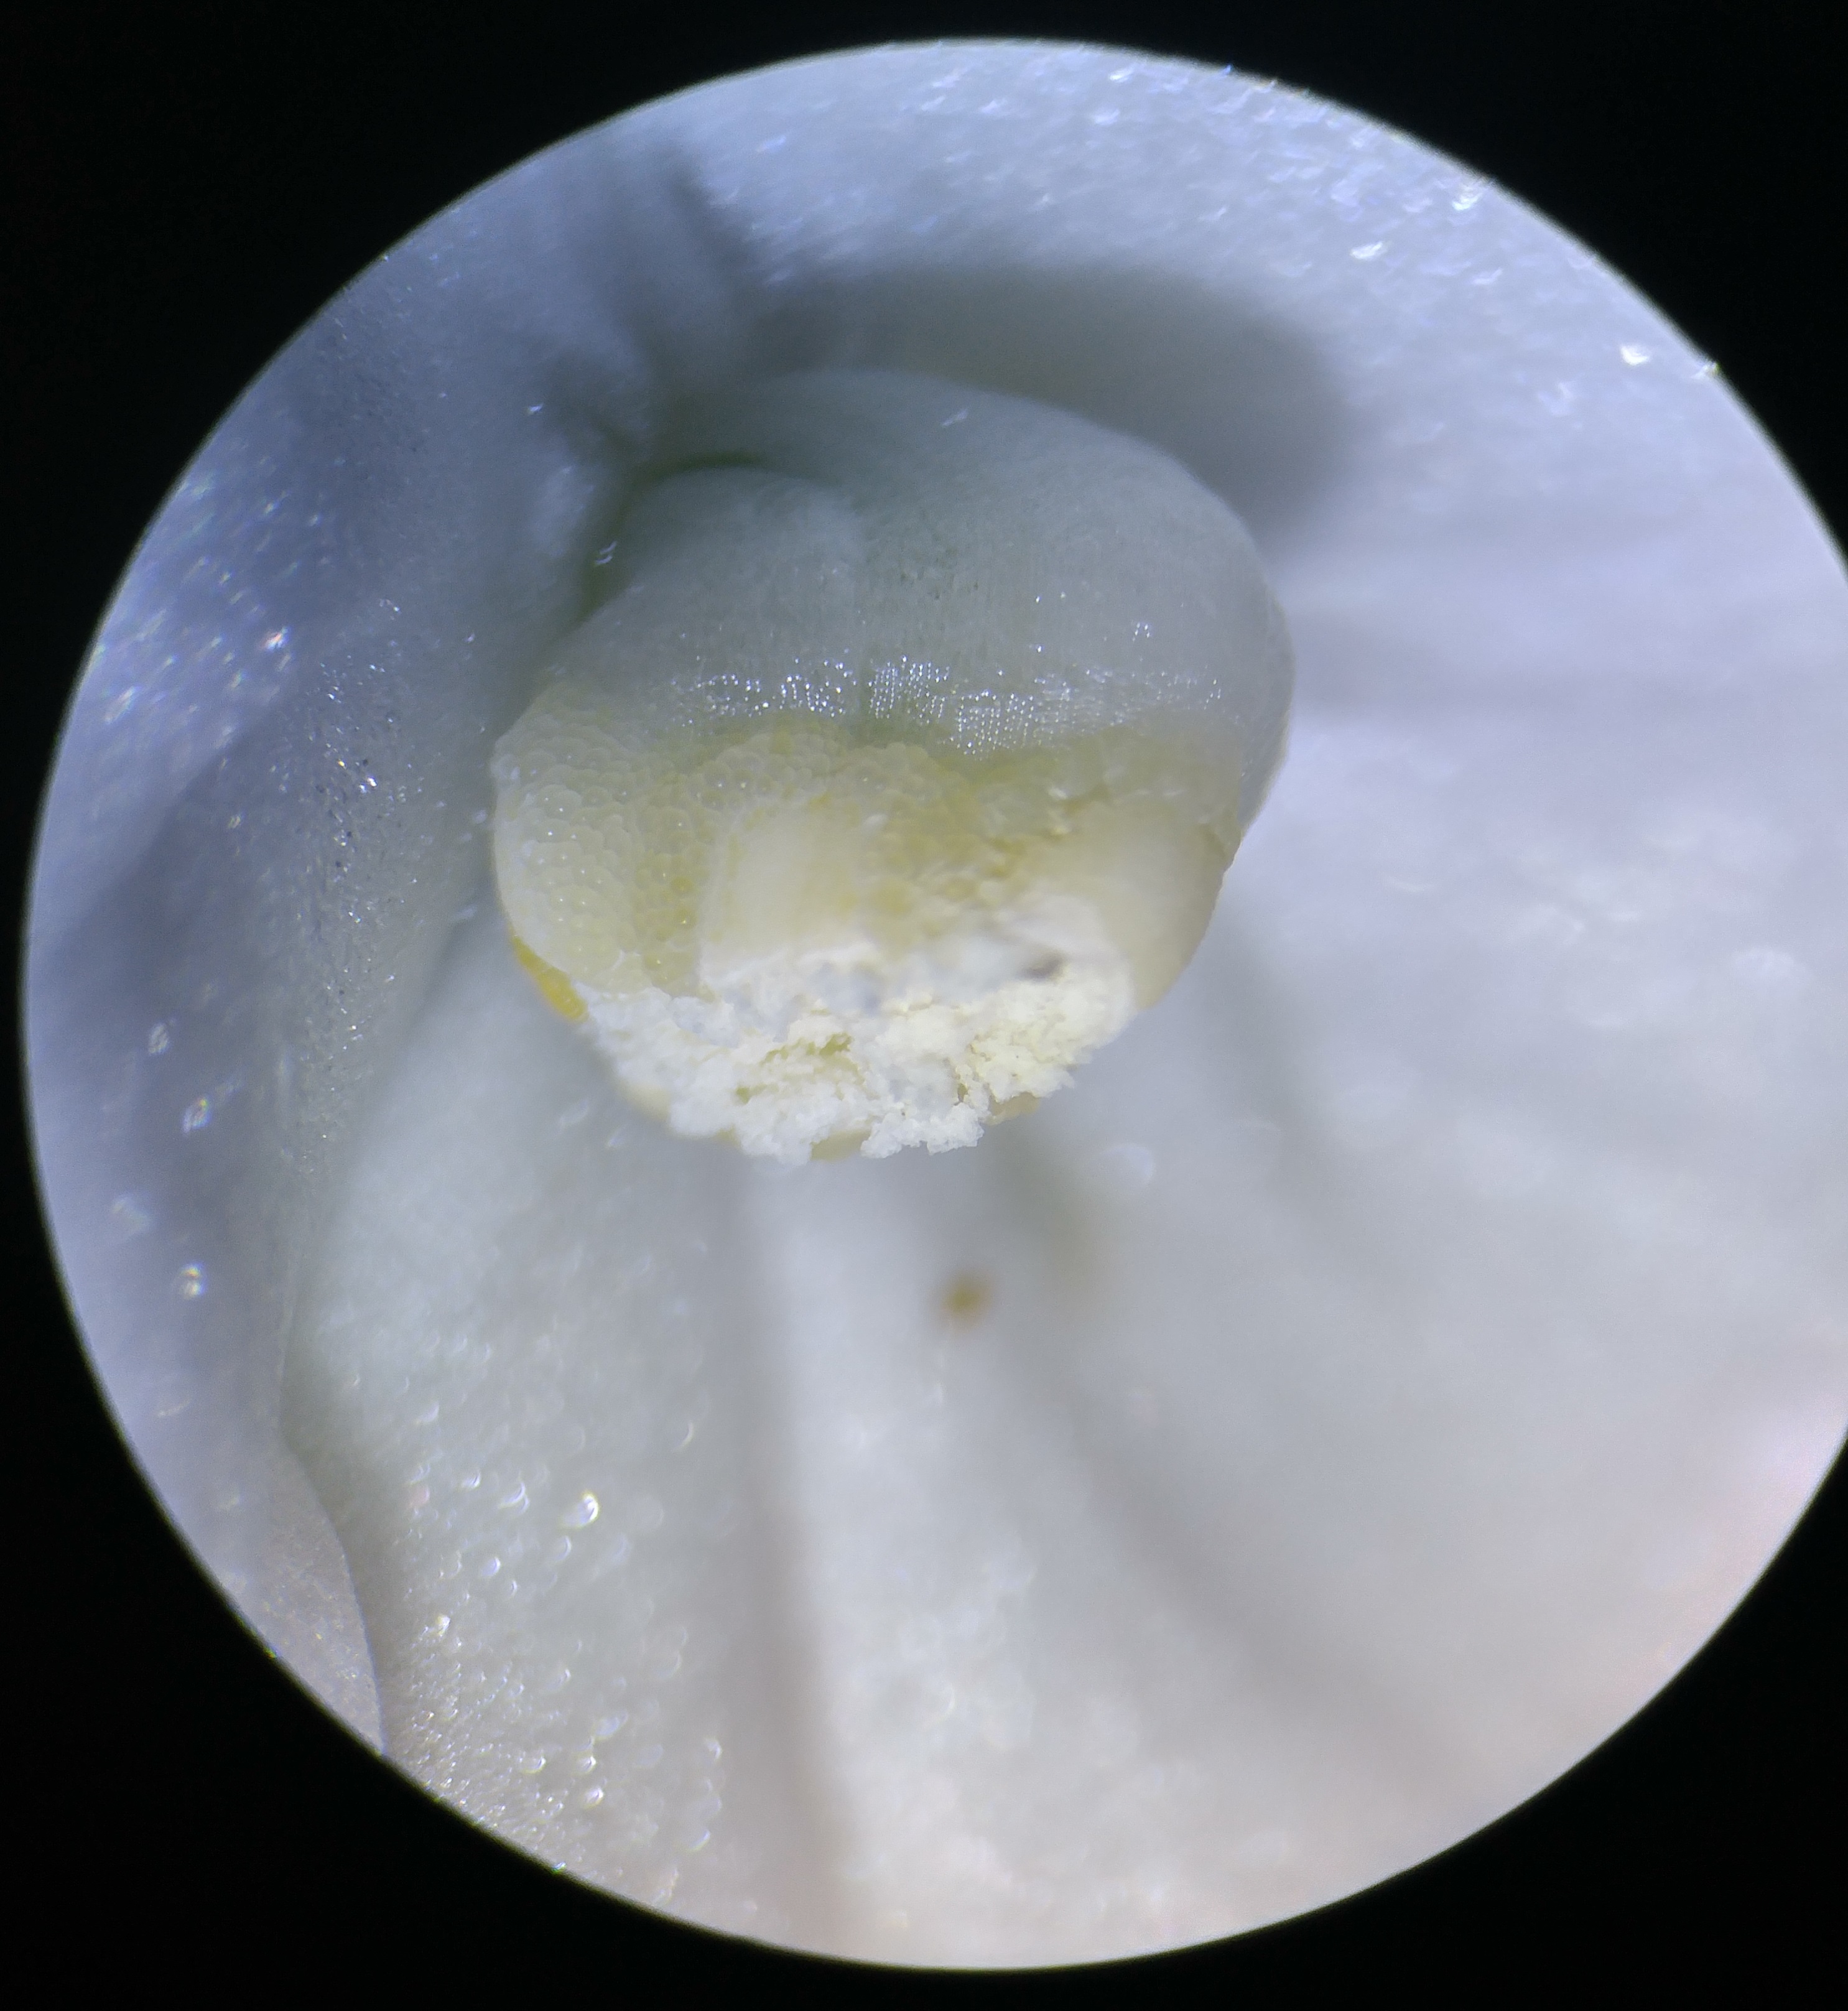

All Rights Reserved. Noah Zalev, 2017